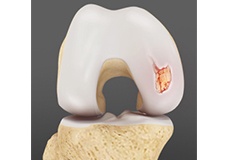

Chondral or Articular Cartilage Defects

The articular or hyaline cartilage is the tissue lining the surface of the two bones in the knee joint. Cartilage helps the bones move smoothly against each other and can withstand the weight of your body during activities such as running and jumping.

Osteochondral Defect of the Knee

An osteochondral defect, also commonly known as osteochondritis dissecans, of the knee refers to a damage or injury to the smooth articular cartilage surrounding the knee joint and the bone underneath the cartilage.